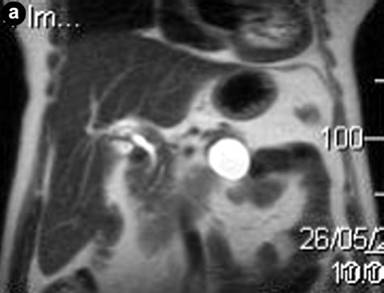

During routine follow-up for a non-functioning left adrenal adenoma (2.0 cm in diameter), a 68-year-old woman underwent a cholangio-Wirsung magnetic resonance and a 4.0 cm cystic unilocular lesion was detected in the pancreatic tail. The cyst had a thickened wall, but not internal septa (Figure 1a). No communication was found with the main pancreatic duct, which was not dilated.

Figure 1. a. The pancreatic tail cyst at MRI scan. b. c. CT scan showing a 4 cm cystic fluid mass arising from the tail of the pancreas, with well defined margins and a lamellar calcification on the posterior wall. |